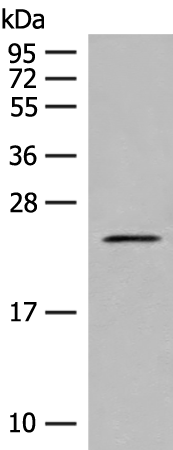

分类: 科研抗体货号: P07150别名:应用: WB,IHC反应种属: Human, Mouse, Rat